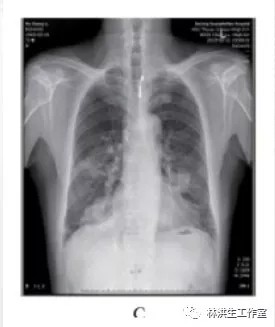

服药 1周后瘙痒减轻,皮疹减少,2个月后复查胸片提示肿瘤稍有缩小,之后继续按原方加减服用中药治疗,定期复查胸片提示肿瘤呈逐渐缩小趋势,同时瘙痒逐渐减轻明显,全身皮疹亦明显好转。2016年6月复查胸片,肿瘤明显缩小,仍有轻微瘙痒、已无皮疹。

C: 2015 年 6 月 21日复查显示双肺肿物进一步缩小;